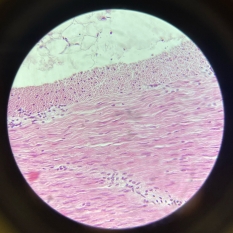

Elastic Arteries (Aorta)

Elastic Arteries (Aorta)

Elastic Arteries (Aorta)